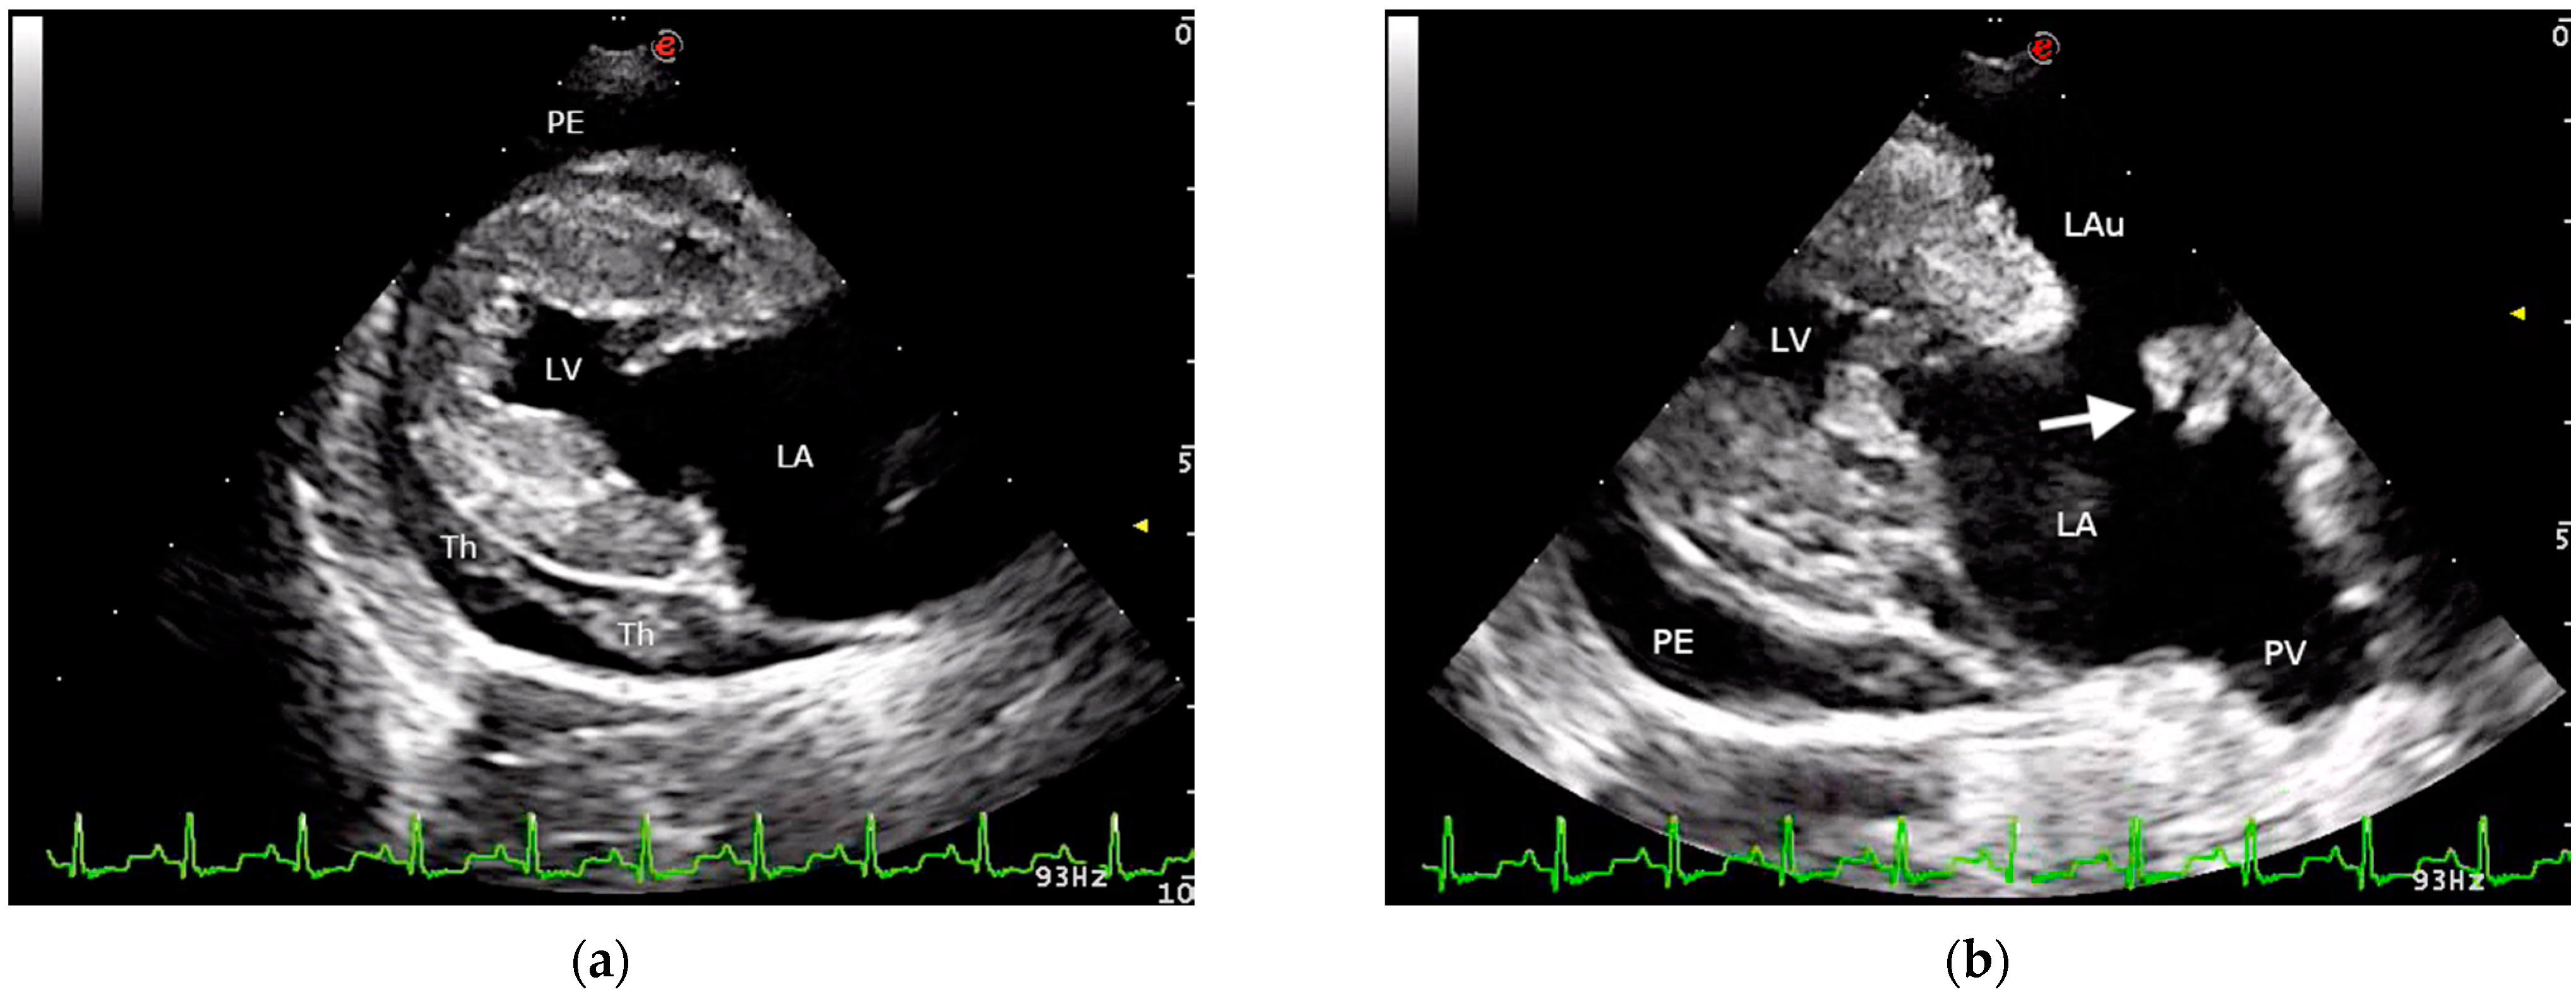

2. Case Presentation